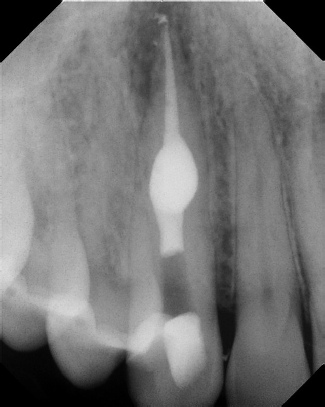

COMPLICATED ANATOMY LARGE LESIONS CALCIFIED CANALS PERFORATION / RESORPTION SEPARATED INSTRUMENTS SURGICAL CASES RETREATMENT / pOST REMOVAL OPEN APICES ACCESS THRU CROWNS Root Canal Case Portfolio

6 mos.